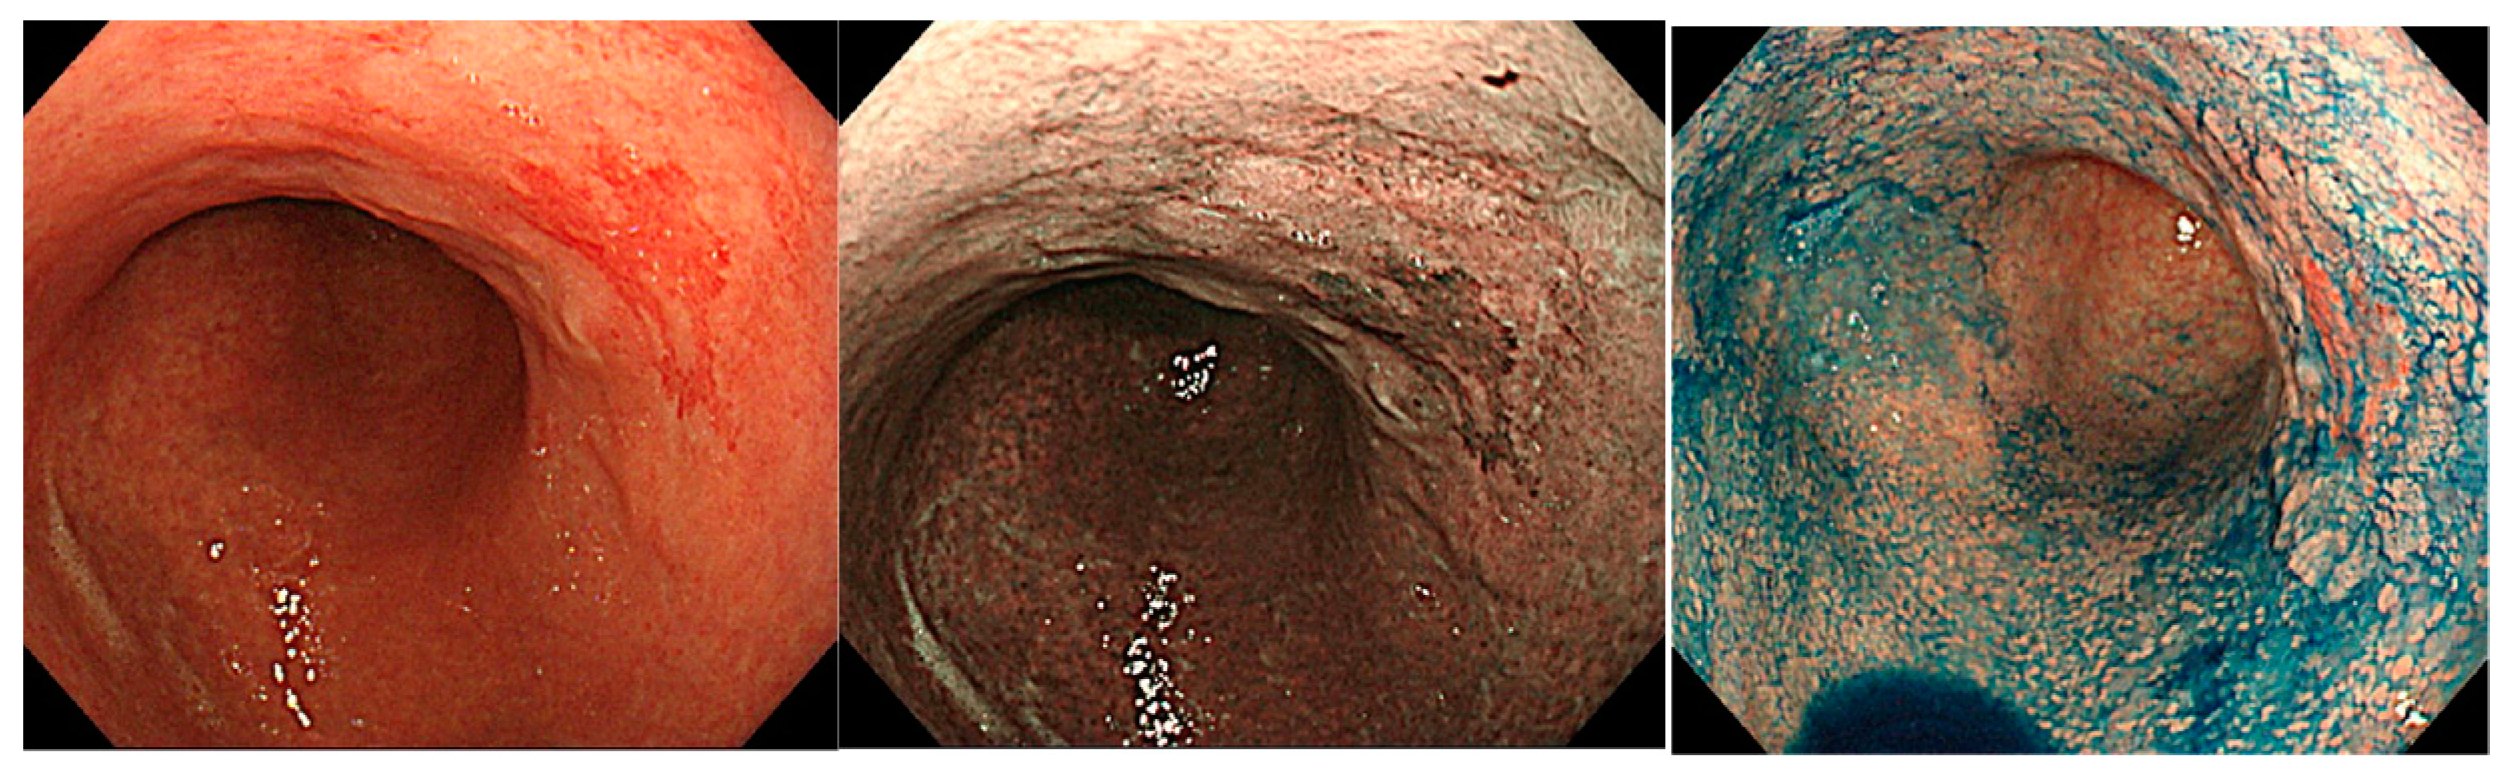

4.2.1. Findings via White Light Observation

4.2.2. Findings via IEE

- Yagi, K.; Nakamura, A.; Sekine, A.; Graham, D. Features of the atrophic corpus mucosa in three cases of autoimmune gastritis revealed by magnifying endoscopy. Case Rep. Med. 2012, 2012, 368160. [Google Scholar] [CrossRef] [PubMed] [Green Version]

- Maruyama, Y.; Yoshii, M.; Kageoka, M. Features of magnifying endoscopic findings in type A gastritis. Stomach Intest. 2018, 53, 1516–1521. (In Japanese) [Google Scholar]

- Kato, M.; Uedo, N.; Toth, E.; Shichijo, S.; Maekawa, A.; Kanesaka, T.; Takeuchi, Y.; Yamamoto, S.; Higashino, K.; Ishihara, R.; et al. Differences in image-enhanced endoscopic findings between Helicobacter pylori-associated and autoimmune gastritis. Endosc. Int. Open 2021, 9, E22–E30. [Google Scholar] [CrossRef] [PubMed]

- Kanzaki, H.; Uedo, N.; Ishihara, R.; Nagai, K.; Matsui, F.; Ohta, T.; Hanafusa, M.; Hanaoka, N.; Takeuchi, Y.; Higashino, K.; et al. Comprehensive investigation of areae gastricae pattern in gastric corpus using magnifying narrow band imaging endoscopy in patients with chronic atrophic fundic gastritis. Helicobacter 2012, 17, 224–231. [Google Scholar] [CrossRef] [Green Version]